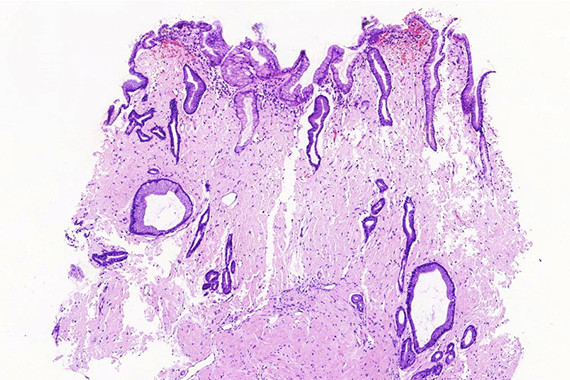

Ultrasound-guided biopsy of a pancreatic lesion in a 38-yeard-old woman (histological and cytological correlation).